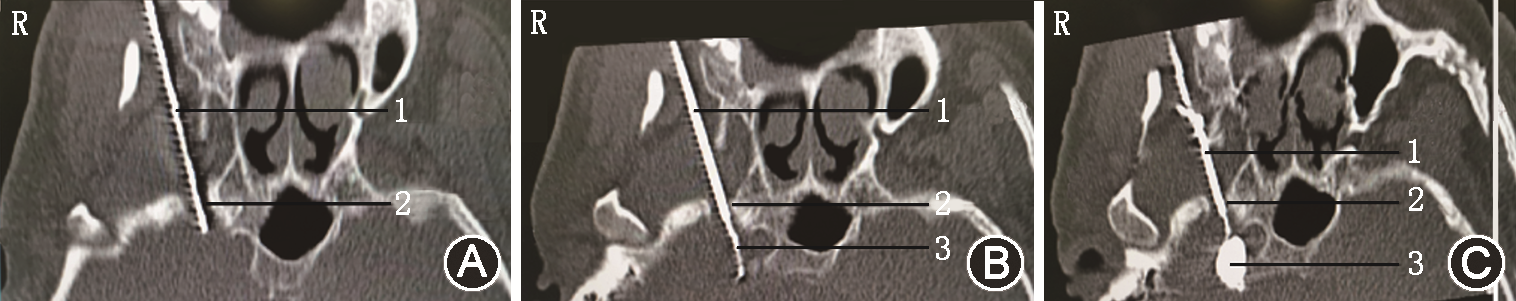

予以原方案继续口服镇痛药物,同时行眶上神经阻滞,利多卡因凝胶贴膏(北京泰德制药股份有限公司,国药准字H20180007,规格:700 mg)外贴,1贴/d,静脉抗生素抗感染、内分泌科会诊稳定血糖。入院调整3 d后,行局部麻醉下CT引导经皮穿刺半月神经节球囊压迫治疗(percutaneous microballoon compression,PMC)[3],因患者有强直性脊柱炎病史,不能平卧,予以多个体位垫辅助固定(图1),术前规划穿刺路径困难(图2)。按经典Hartel入路穿刺进入卵圆孔内口(图3A)[4],退出针芯,置入球囊导管,使远端Mark点与岩锥顶端平齐(图3B),注入30%碘海醇造影剂0.6 ml充盈球囊(图3C),球囊CT三维影像成“梨”形(图4),压迫半月节200 s,询问患者自诉右面部皮肤感觉轻度麻木,原疼痛基本消失,NRS评分2分,遂释放球囊内造影剂,拔出于球囊导管和穿刺针,结束手术。